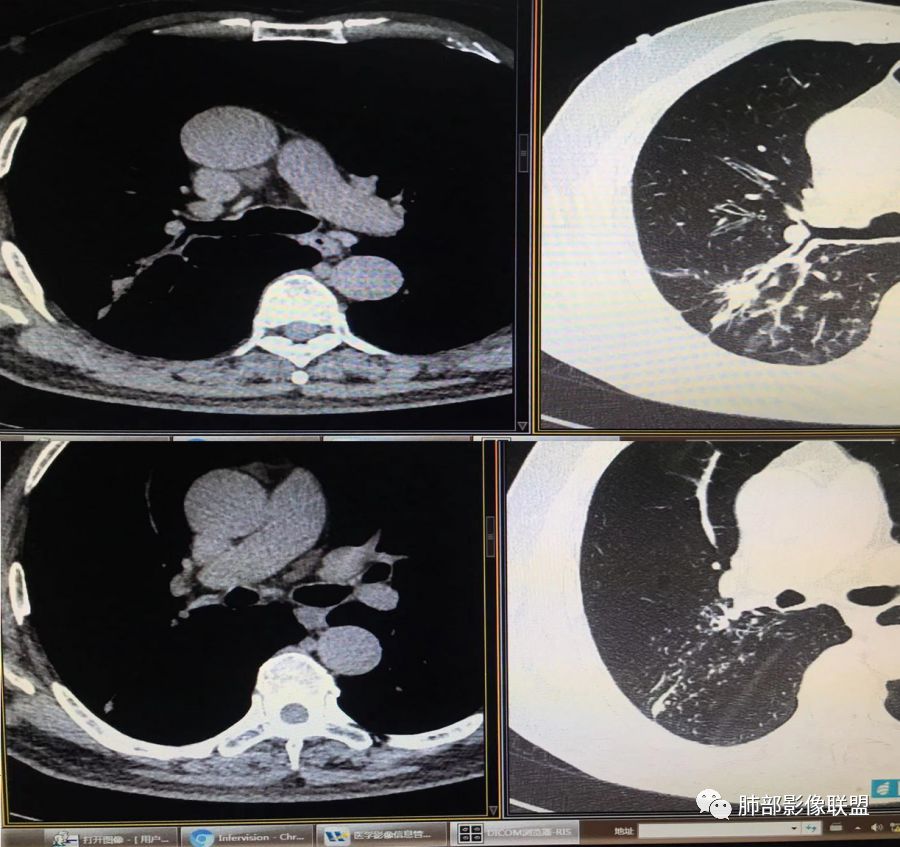

胸CT示病变位于右肺上叶,右肺上叶前段支气管壁不规则增厚狭窄、远端扩张。右肺上叶后段实变影,纵隔窗实变内可见钙化灶,可见支气管引流征,引流支气管壁明显增厚,边缘可见短硬毛刺,胸膜牵拉,u型征,周围可见卫星灶,并可见支气管扩张及其管壁增厚;病灶整体存在膨胀性生长。考虑良性病(结核)变基础上合并癌变,腺癌?

患者中老年男性,咳嗽喘息半年。查体双肺闻及哮鸣音。胸部CT:右肺上叶后段不规则结节灶,可见长毛刺、胸膜牵拉、分叶及钙化征象,周围见点片状卫星灶,近端支气管壁增厚,呈支气管爬行征。综合考虑结核。鉴别恶性病变。

老年男性,咳嗽半年,右肺上叶后段实性结节伴粟粒状卫星灶,结节内有钙化,部分边缘平直,周围见长索条,有胸膜牵拉,结核是明确的,常规需要增强判断有无合并肺癌,当然该患者已经穿刺。

右肺上叶后段结节,点状钙化,边缘见细长毛刺,胸膜凹陷,卫星灶伴树芽症,支气管壁增厚扩张,有截断,考虑结核,但腺癌没法排除,确实有增强就基本能明确。

右肺上叶后段结节,长毛刺、钙化灶、近端小空洞、索条影、周围支气管树丫、引流支气管增厚,主体病灶侧后方分隔样空腔,弥漫支气管增厚,大气道受累,支持感染的征象较多,TB、曲霉;分叶、膨隆、脊状凸起、毛刺等恶性征象也有,遗憾没看到增强,只有期待活检一槌定音。

老年男性,咳嗽半年,右肺上叶后段实性结节,内见钙化,边缘部分膨隆,有长短毛刺、分叶、空泡征,胸膜侧见胸膜牵拉,周围不干净,见小卫星灶,右上叶后段支气管管壁增厚,扩张,有炎性及恶性征象,一元论常规考虑炎性肉芽肿病变,结核可能,腺癌不除外,二元结核并腺癌,建议增强及穿刺活检。

右上肺后段结节,边界清晰,可见分叶及毛刺,血管集束征,胸膜牵拉,内见斑点状钙化,周围见斑点状模糊影,同时伴支气管扩张,管壁增厚。整体感觉恶性征象多于良性,首先考虑肺癌,鉴别肉芽肿性病变,结核位置不像。

右肺上叶后段团块影,内见钙化,周围胸膜有牵拉,近段支气管扩张管壁增厚,周围可见卫星灶,右支气管狭窄,综合考虑支气管内膜结核,鉴别真菌感染(气道侵袭性曲霉菌病)。

右上后段结节,整体收缩,长软毛刺丶胸膜凹陷,有点状钙化丶小空洞,引流支气管明显管壁增厚,周边卫星灶明显,有喘息史半年,可能有应用激素史,致内源性复发,考虑TB,鉴别腺癌。

(右肺肿物穿刺)肺腺癌,贴壁生长型为主,少部分为腺泡型。

3.本例病灶影像表现为:右肺上叶后段不规则结节灶,病灶整体存在膨胀性生长,可见毛刺、胸膜牵拉、分叶及钙化征象,近心端小空洞,周围见点片状卫星灶并出现磨玻璃影,近端支气管壁增厚,管腔扩张,既有恶性征象,也有结核的征象。南边老师考虑结核与腺癌同时存在,但遗憾的是缺乏增强扫描图像,亦未提供结核相关辅助检查结果。